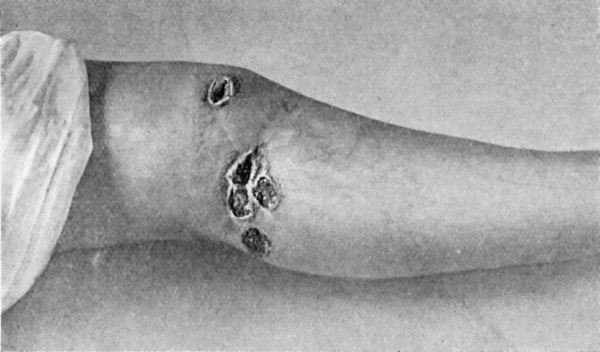

38.Primary Lesion on Thumb, with Secondary Eruption on Forearm 154

39.Syphilitic Rupia 159